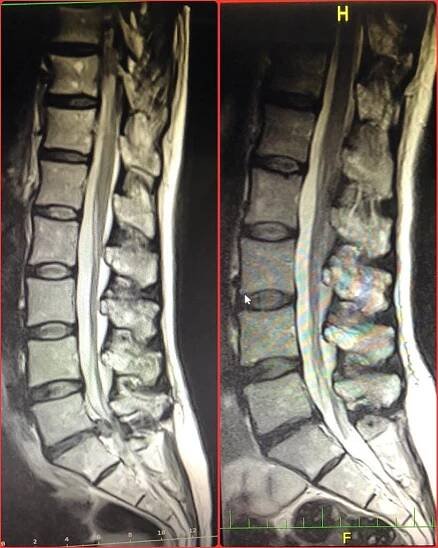

Ploténka se vysune do nesprávné pozice a utlačuje nervy míchy. Nejčastěji se to stává v oblasti krční a bederní páteře.

Vyhřezlá ploténka, odborně známá jako hernie disku, je stav, při kterém část ploténky vyčnívá mimo své normální místo mezi obratli. Při tom může tlačit na sousední nervy, což způsobuje bolest, necitlivost nebo slabost v přidružených oblastech, do kterých skřípnutý nerv vede. Nejčastěji se objevuje v oblasti…

Vyhřezlá ploténka vzniká, dojde-li k narušení a vytlačení jejího gelovitého jádra, což následně vede k tlaku na okolní nervy nebo míchu a s tím spojené bolesti.